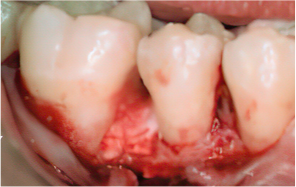

Before & After

엠도게인 수술과정

-

STEP 01

잇몸을 절개

STEP 02

Scaling Root Planning을 실시

STEP 03

치석 및 치태 등 제거

STEP 04

엠도게인 도포

STEP 05

클렌징

STEP 06

판막을 봉합